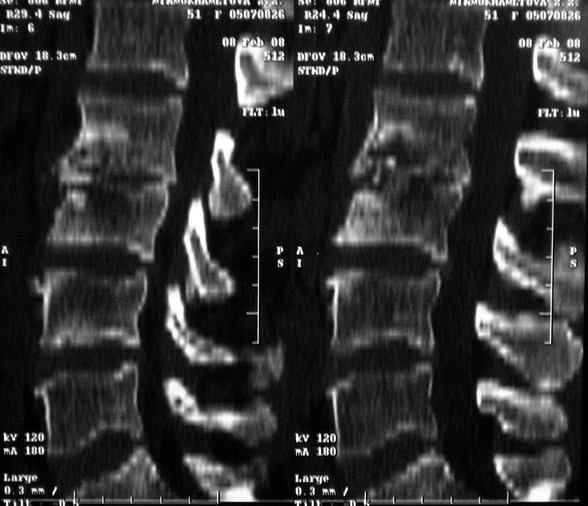

Отправляю MRI в динамике, снятые с пленки на фотоаппарат.

|

MRI через три недели

По данным представленных КТ и МРТ у больной имеется достаточно выраженная степень деструкции тел позвонков (около 30% общей костной массы тела позвонка), что определяет высокий риск возникновения патогических переломов и появления локальной кифотической деформации на этом уровне.